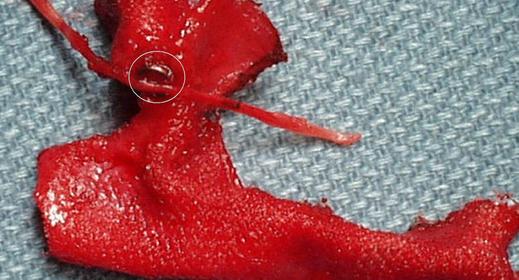

Przyczyną nieznośnego bólu może być złe umocowanie siatki – np. użycie nie wchłaniających się zszywek. Obok zdjęcia z usuwania siatki z mocowanej metalowymi zszywkami, które (co oczywiste) bolały chorego. Ból, uczucie stałej przeszkody był nie do wytrzymania. W czasie operacji okazało się, że metalowych zszywek jest bardzo dużo, były ostre, kłuły. Sama siatka była sztywna i niedopasowana do ciała młodego człowieka. Jedynym rozwiązaniem było usunięcie siatki z zszywkami.

Usuwanie siatki to zwykle rozległa operacja i ciało jest okaleczone. Po usunięciu siatki może powstać nawrót przepukliny. Nie wykluczone, że chorego czeka kolejna operacja; na siatkę już się nie zdecyduje.